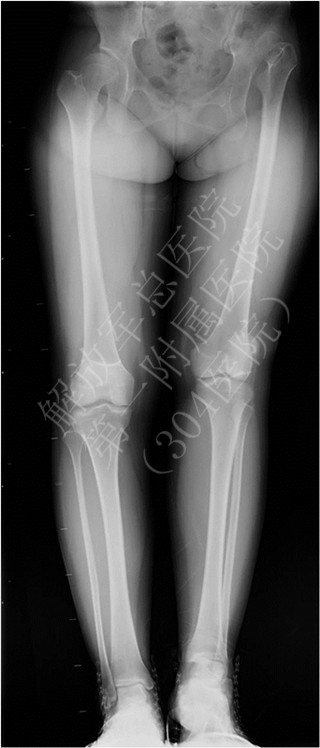

以外观异常为主要表现,无胸闷、气喘,无下肢无力。入院查体神经学检查未见明显异常。影像学结果提示:胸段脊柱右侧凸,cobb角38度;腰段脊柱左侧凸,cobb角58度,;矢状面曲度基本正常;躯干偏移3.8cm,Risser征Ⅳ度。Bending像结果提示胸弯柔韧性73%,腰弯柔韧性82%;腰4/5椎间隙可自由开放;反向Bending像提示腰4下终板与双髂嵴连线成角8度。全脊柱MRI未见异常,特发性脊柱侧凸诊断明确,PUMC分型应为ⅡC1型。

患者腰弯达到58度,存在进一步进展的可能,手术指征明确。 术前主要考虑问题: 1、融合范围:考虑患者年龄已16岁,Risser征Ⅳ度,脊柱自我矫正能力较差,行选择性融合出现躯干失代偿的可能性较大,因此对该患者倾向于融合双弯。 2、远端融合椎的选择:根据Bending像检查结果,腰4/5椎间隙可自由开放,反向Bending像腰4下终板与双髂嵴连线成角小于15度,且大部分落在稳定区内,旋转小于Ⅱ度,因此远端融合椎可选择腰4。保留腰4/5节段有助于保留腰部运动功能,提高代偿能力,减少今后出现腰痛的几率。 最终在全麻下为患者行后路侧凸矫形,胸5-腰4椎弓根钉、植骨融合术。手术时间3小时,术中出血300ml。术后下肢运动正常,复查X线提示胸弯矫正至8度,腰弯矫正至6度,躯干偏移恢复良好,矫形效果满意。